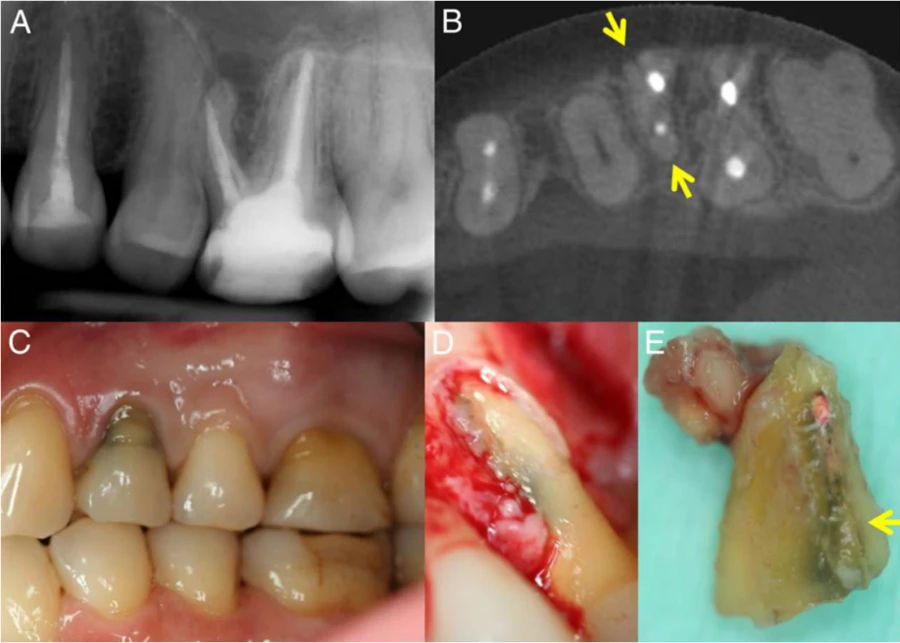

Ảnh 1: Răng 14 đã điều trị nội nha, được nghi là có VRFỞ thời điểm khám, răng không nhạy cảm với bộ gõ, không xuất hiện viêm sưng hay túi lợi.

(A) PR kỹ thuật số; có thể nhìn thấy hình ảnh phóng xạ quanh gốc xung quanh rễ trung bì.

(B) Hình chiếu trục của cùng một răng; có thể nhìn thấy một vạch phóng xạ ở mặt ức và vòm miệng (mũi tên) của rễ trung bì.

(C) Ảnh chụp trước phẫu thuật.

(D) Bề mặt chân răng lộ ra sau khi nâng vạt.

(E) Đường nứt có thể nhìn thấy (mũi tên) ở rễ trung bì được cắt bỏ.